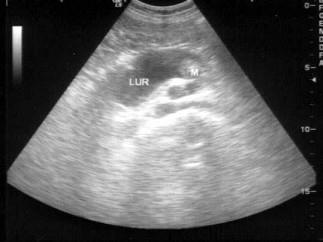

问题 男,63岁,因左侧腰部疼痛不适伴无痛血尿1月余就诊,B超显示左肾集合系统分离3.9cm,如图所示,最可能的诊断为?(?)

选项 A.左输尿管结石 B.左输尿管癌 C.左输尿管炎性狭窄 D.左输尿管畸形 E.左输尿管血块

答案 B